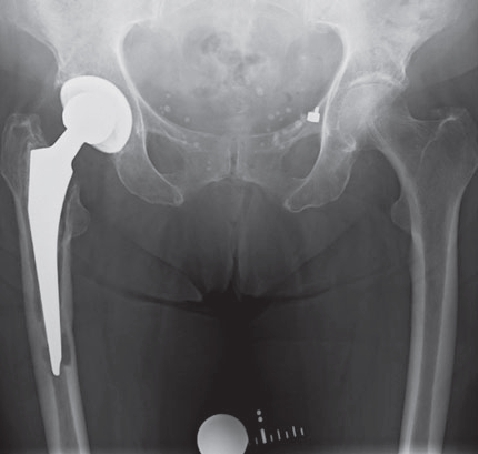

However, infections often go unnoticed for many weeks, so that removal of the prosthesis is unavoidable. Depending on the pathogen and its sensitivity, a placeholder containing antibiotics is then implanted, which remains in place for 6 weeks. Antibiotics in tablet form must then also be taken for this period. However, it is not necessary for a patient to remain in the hospital during this entire period. If home care is not possible, for example, it is also possible to organize this in close cooperation with our social services. After 6 weeks it is generally possible to reimplant a prosthesis, provided that the blood values show that the infection is under control. Antibiotics must then be taken again for 6 weeks after surgery. Which antibiotics are taken is determined in close cooperation with colleagues in microbiology and clinical pharmacology, with whom regular rounds and therapy checks are carried out. These therapeutic measures are carried out in a special area of the clinic using the most modern methods.

Infizierte HüfttotalendoprotheseKniegelenkinfektion nach EndoprotheseImplantierte Spacer nach ProthesenentfernungVorgefertigte Spacer (Platzhalter) mit Antibiotika